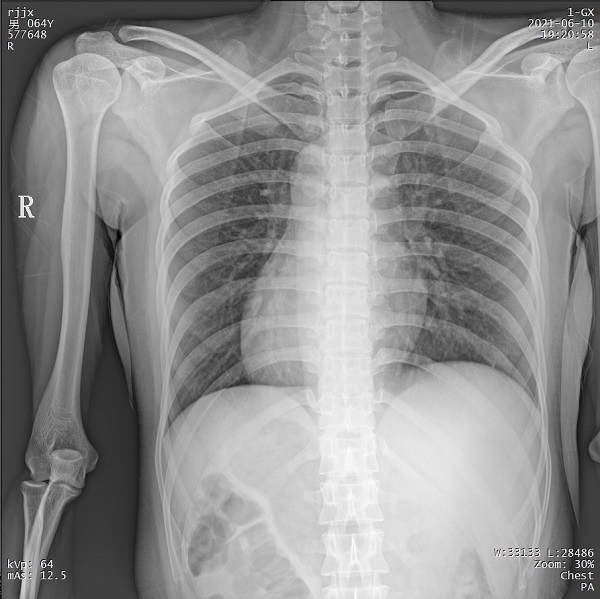

PLX5500系列移動(dòng)DR能夠在1ms的曝光時(shí)間內(nèi)輸出足量的X射線,獲取清晰圖像。特別適用于拍攝肺炎、塵肺病、肺結(jié)核等難以憋氣的患者,避免了因患者肺部呼吸運(yùn)動(dòng)而產(chǎn)生的運(yùn)動(dòng)偽影的影響,瞬間定格清晰圖像,以供醫(yī)生準(zhǔn)確診斷。

三、支持高千伏攝影 肺部紋理更有層次

PLX5500系列移動(dòng)DR的可調(diào)千伏達(dá)到150kV,在達(dá)到一定高電壓后,與骨骼相重疊的軟組織或骨骼本身的細(xì)小結(jié)構(gòu)及含氣的管腔等,均可清晰顯示。